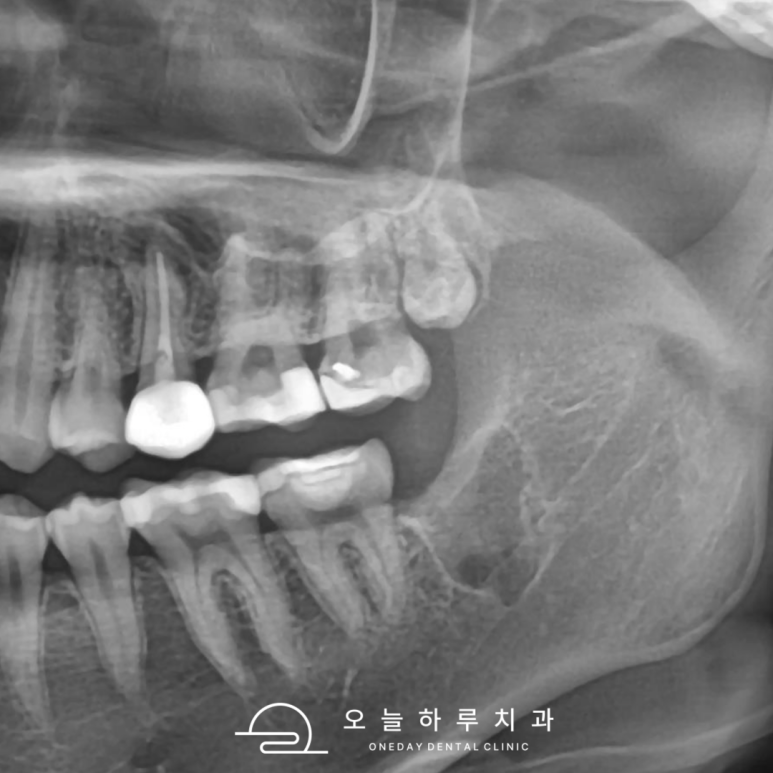

📷 오늘하루치과는

3D CT, 디지털 엑스레이, 구강 사진 촬영 등

정확한 영상 진단을 기반으로

발치 여부를 상담드립니다.

⚠️ 하악 사랑니, 특히 주의하세요

특히 아래턱(하악) 사랑니는

하치조신경과 가까이 위치해 있어서

발치 시 더욱 신중해야 합니다.

🔎 문정동치과 오늘하루치과는

CT 촬영을 통한 신경 위치 확인 후

발치 난이도까지 사전에 예측하여 안내드립니다.